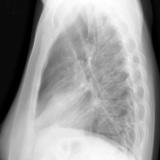

Case 1 Lateral

Date: 02/28/2004

Views: 3195